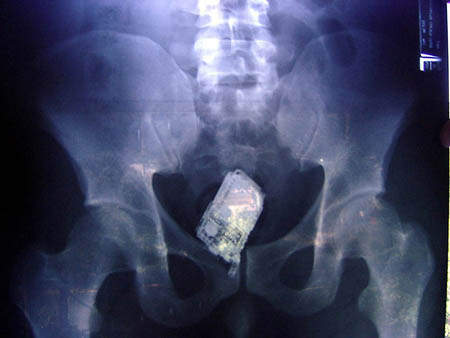

囚犯腸內的手機

圖片來自:http://www.po-kaki-to.com/